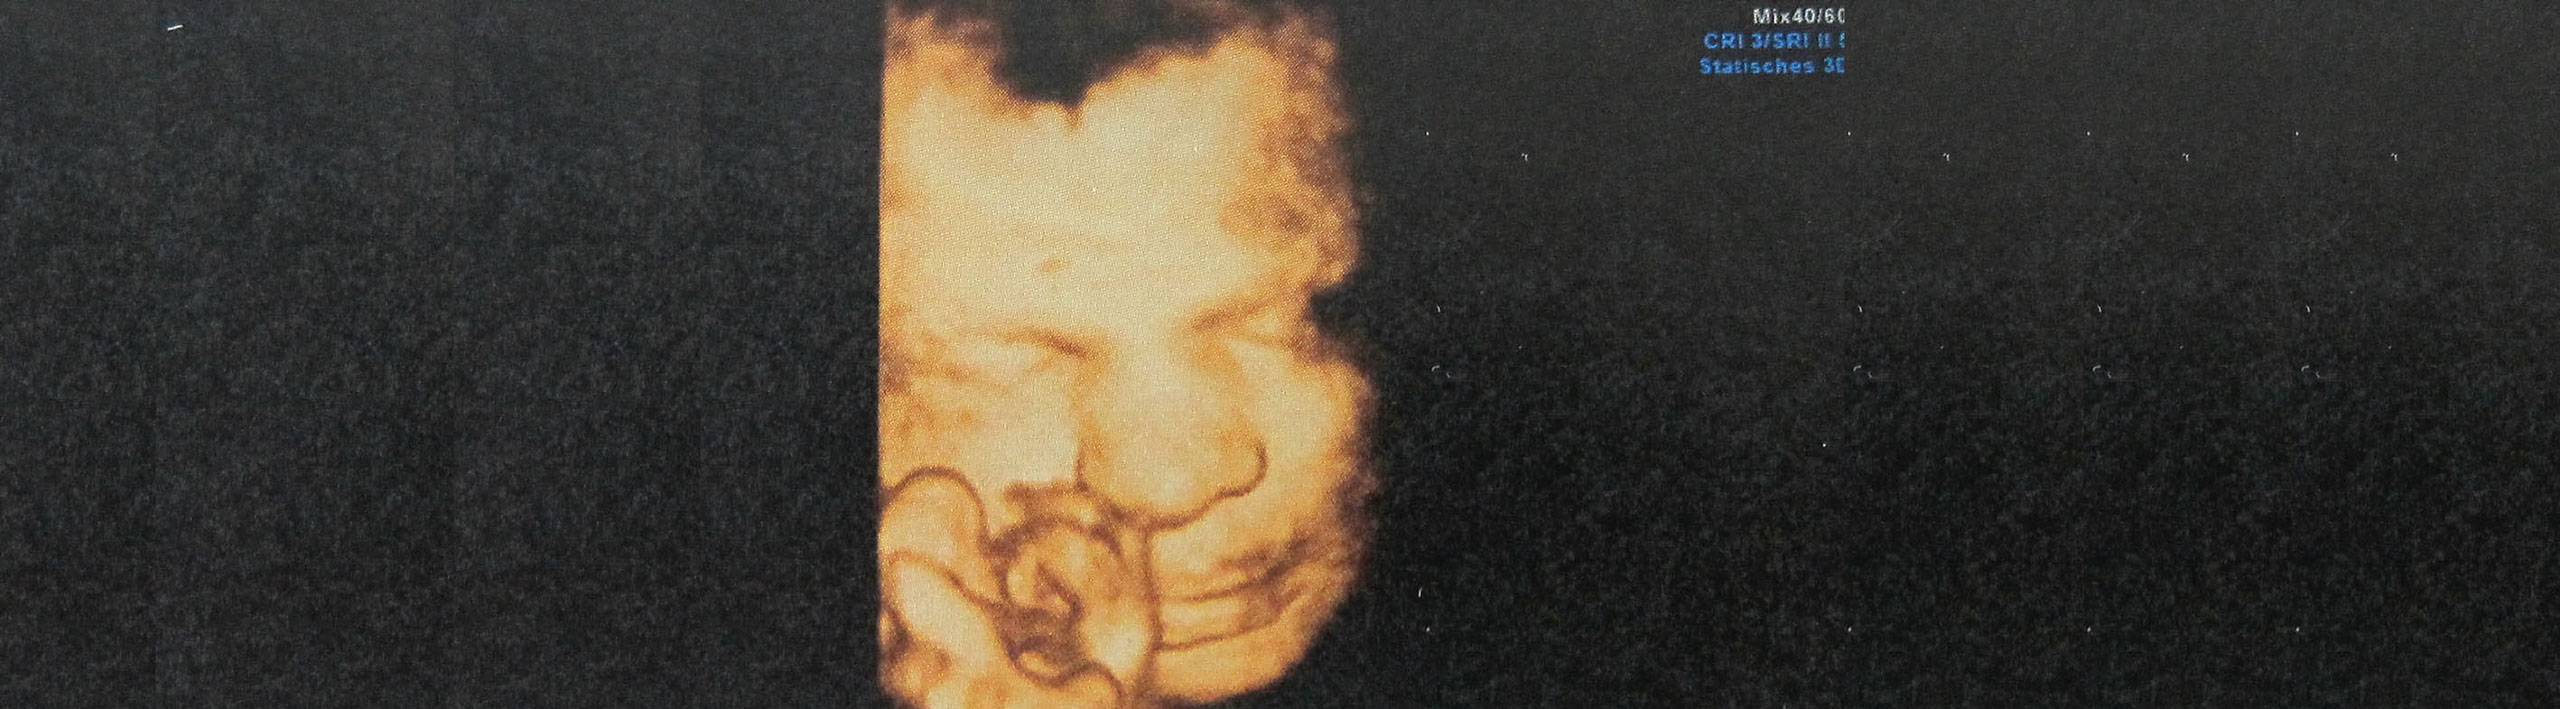

Frühkindliche Prägung bereits im Uterus - auch der zukünftigen Ernährung

Nach 10jähriger Tätigkeit an der Universitätsklinik Frankfurt a.M. (in der Kinderheilkunde und speziell auch Neugeborenenmedizin) betätige ich mich jetzt seit über 15 Jahren nur noch  in der Präventionsmedizin.

Da dies zu Beginn des Lebens , also während der Schwangerschaft, für die Primärprävention die Erfolgsaussichten erhöht, gilt mein besonderes Engagement  neben den Kindern, den Müttern in der Schwangerschaft.